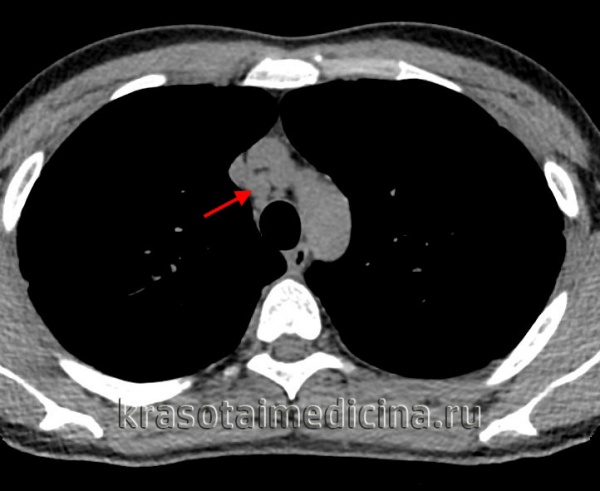

• Компьютерная томография (КТ) органов грудной клетки:

- При КТ органов грудной клетки можно выявить лимфадепопатию или гранулематозную инфильтрацию.

- Другие признаки могут включать наличие малых узелков с бронховаскулярной или субплевральной локализацией, утолщение междолевой плевры, легочную ткань в виде «медовых сот», бронхоэктазы и альвеолярную консолидацию.

КТ органов грудной клетки. Множественные типичные саркоидозные очаги субмиллиметрового диапазона с диффузным распространением